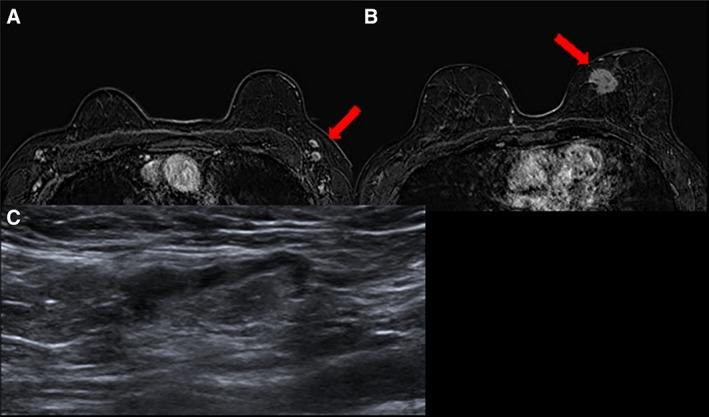

The detection of lymph node metastasis affects the management of patients with primary breast cancer significantly in terms of staging, treatment, and prognosis. The main goal for the radiologist is to determine and detect the presence of metastatic disease in nonpalpable axillary lymph nodes with a positive predictive value that is high enough to initially select patients for upfront axillary lymph node dissection. Features that are suggestive of axillary adenopathy may be seen with different imaging modalities, but ultrasound is the method of choice for evaluating axillary lymph nodes and for performing image-guided lymph node interventions. This review aims to provide a comprehensive overview of the available imaging modalities for lymph node assessment in patients diagnosed with primary breast cancer. IMPLICATIONS FOR PRACTICE: The detection of lymph node metastasis affects the management of patients with primary breast cancer. The main goal for the radiologist is to detect lymph node metastasis in patients to allow for the selection of patients who should undergo upfront axillary lymph node dissection. Features that are suggestive of axillary adenopathy may be seen with mammography, computed tomography, and magnetic resonance imaging, but ultrasonography is the imaging modality of choice for evaluating axillary lymph nodes. A normal axillary lymph node is characterized by a reniform shape, a maximal cortical thickness of 3 mm without focal bulging, smooth margins, and, depending on size, a discernable central fatty hilum.

临床意义